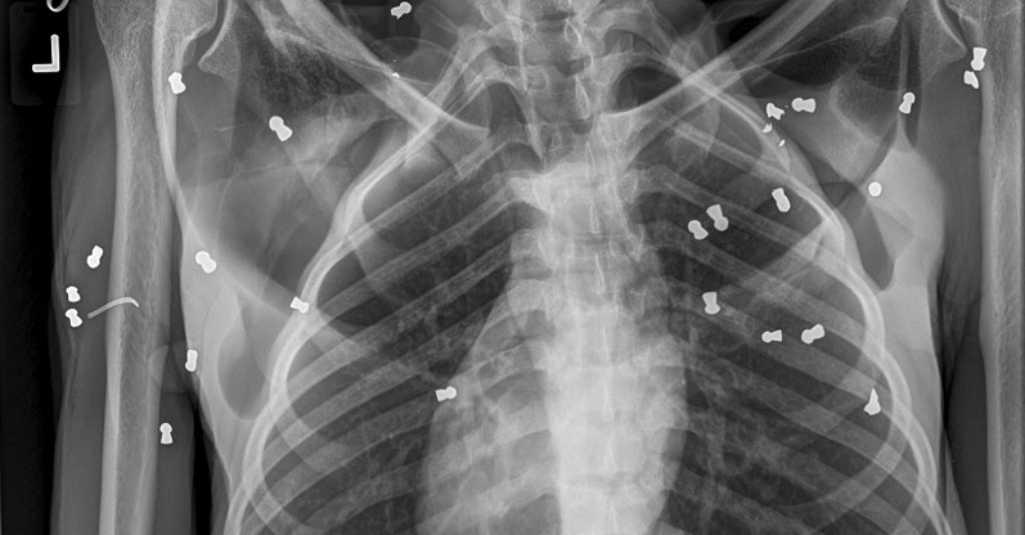

Hasil pemeriksaan dokter hewan terhadap induk orang utara itu, ditemukan 74 butir peluru senapan angin. Peluru senapan angin juga membutakan kedua mata induk orang utan tersebut.

Kondisi induk orang utan itu saat dievakuasi dalam keadaan luka parah pada kaki, tangan, dan badan, diduga akibat benda tajam. Mata induk orang utan tersebut terluka akibat peluru senapan angin.

Sapto Aji mengatakan, adanya peluru di tubuh orang utan membuktikan bahwa senapan angin digunakan menembak orang utan. Padahal, orang utan merupakan satwa yang harus dilindungi.